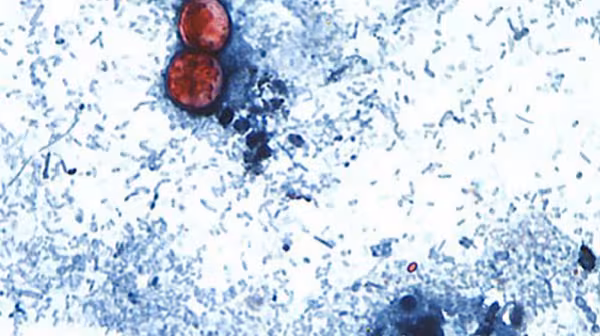

Cyclospora cayetanensis is a unicellular parasite that causes an intestinal infection called cyclosp...